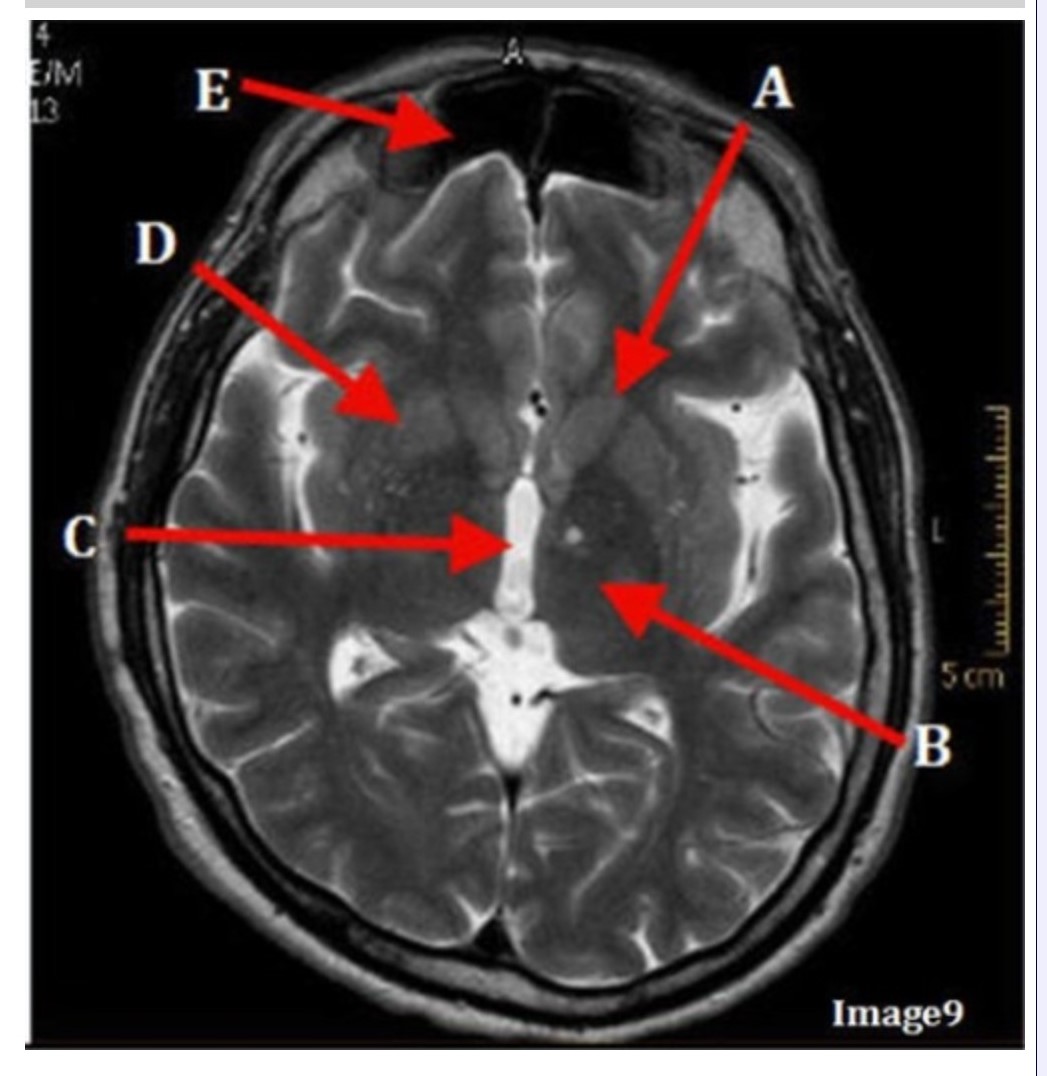

Letter C in Image 9 is pointing to:

A. Third ventricle

B. Thalamus

C. Lentiform nucleus

D. Caudate nucleus

Letter B in Image 9 is pointing to:

A. Third ventricle

B. Thalamus

C. Lentiform nucleus

D. Caudate nucleus

Letter D in Image 9 is pointing to:

A. Third ventricle

B. Thalamus

C. Lentiform nucleus

D. Caudate nucleus

Letter E in Image 9 is pointing to:

A. Maxillary sinus

B. Sphenoid sinus

C. Frontal sinus

D. Ethmoid sinus

Letter A in Image 9 is pointing to:

A. Third ventricle

B. Thalamus

C. Lentiform nucleus

D. Caudate nucleus

Image 9 is an example of a _____ weighted sequence acquired in the _______ scan plane.

A. T1; Axial

B. T2 FLAIR; Sagittal

C. T2; Axial

D. T2; Coronal